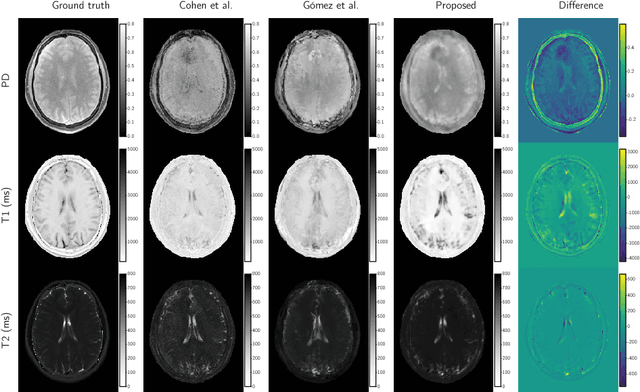

Magnetic resonance fingerprinting (MRF) quantifies multiple nuclear magnetic resonance parameters in a single and fast acquisition. Standard MRF reconstructs parametric maps using dictionary matching, which lacks scalability due to computational inefficiency. We propose to perform MRF map reconstruction using a spatiotemporal convolutional neural network, which exploits the relationship between neighboring MRF signal evolutions to replace the dictionary matching. We evaluate our method on multiparametric brain scans and compare it to three recent MRF reconstruction approaches. Our method achieves state-of-the-art reconstruction accuracy and yields qualitatively more appealing maps compared to other reconstruction methods. In addition, the reconstruction time is significantly reduced compared to a dictionary-based approach.